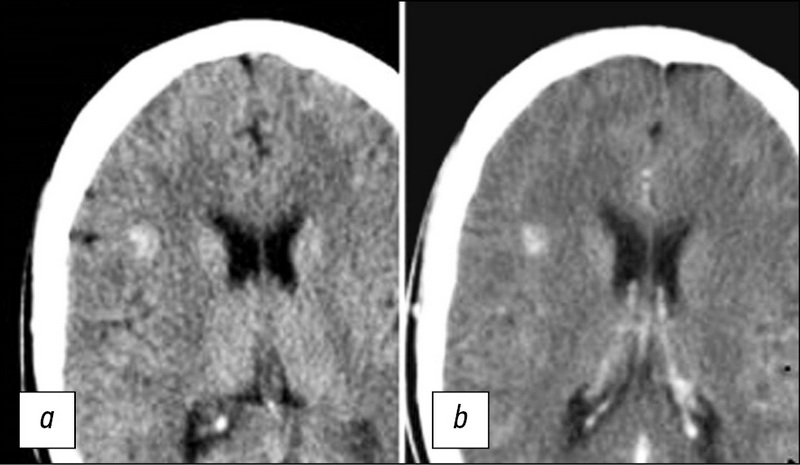

脑洞畸形的放射诊断

目前,脑海绵状畸形是相当普遍的血管病理:近年来发现的病例数量急剧增加。这是由于将其引入临床实践并广泛传播了现代神经成像方法,例如计算机断层扫描(CT)和磁共振成像(MRI)断层扫描。CT和MRI出现之前,很难诊断出这种病理,诊断通常是在术中或根据尸检数据进行的。文献综述致力于脑海绵状畸形(CM)的放射学诊断。分析了神经影像学方法对海绵状畸形的诊断的重要性,以及使用MRI对骨髓进行可视化的重要性。相比于这种病理学的其他神经影像学检查方法,MRI具有优势。根据形态学底物,对MRI的脉冲序列和各种类型灶的信号特征进行了表征。分析 SWI (susceptibility weighted imaging)序列的值 用于检测家族性CM病例中的多灶性病变。对MRI的主要脉冲序列进行可视化以研究海绵状畸形的研究将有助于优化协议算法,以便及时诊断这种病理状况并选择治疗策略。